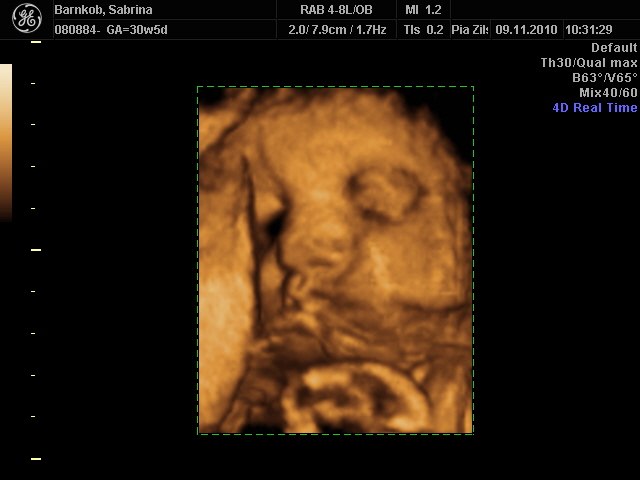

Så må jeg hellere smide en update på maven det er efterhånden længe siden jeg har lagt et billede ind. Vi har været til to 3D scanninger, da den første blev meget mislykket, hun ville kun ligge med hovedet ind i moderkagen og putte   sidste uge var vi så afsted igen og der fik vi liiidt gode billeder af hende, det var en fantastisk oplevelse, vi så hun suttede på finger, gabte og smilte ud til os   Billedet jeg har lagt med er nok det bedste vi har fået og der kan man tydeligt se moderkagen til venstre  I morgen skal jeg til vækstscanning på hvidovre og tale med en fødselslæge om pks, og nok få den endelige dato, uhhhh det bliver spændende   Det andet billede er fra i går til min nieces barnedåb.